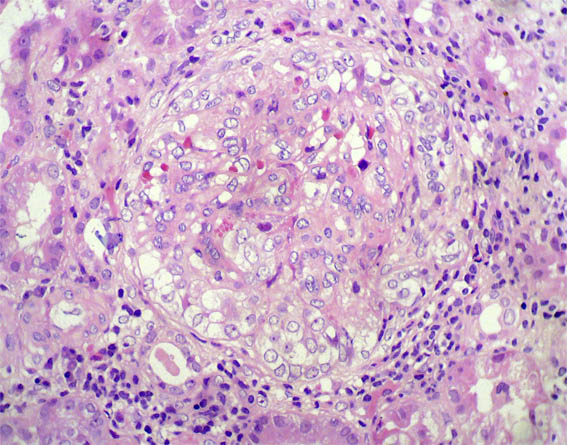

Figure 2.

H&E, X200.